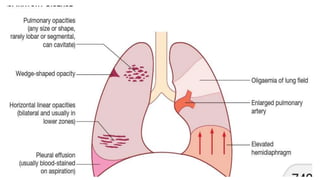

CXR

Chest radiograph findings in patient with pulmonary embolism

Result

Cardiomegaly

Normal study

Atelectasis

Elevated Hemidiaphragm

Pulmonary Artery Enlargement

Pleural Effusion

Parenchymal Pulmonary Infiltrate

Diagnostic Tests CXR Chest radiographfindings in patient with pulmonary embolism Result Cardiomegaly Normal study Atelectasis Elevated Hemidiaphragm Pulmonary Artery Enlargement Pleural Effusion Parenchymal Pulmonary Infiltrate